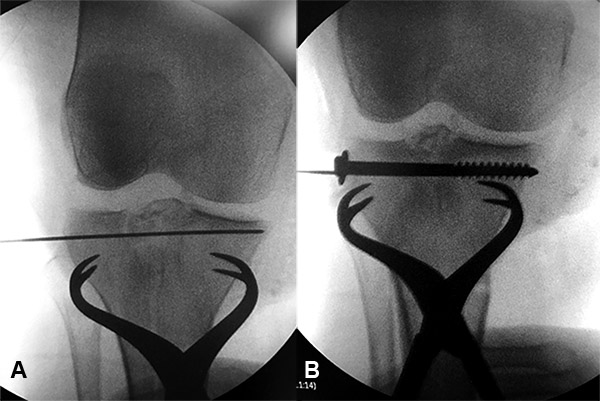

Posteriormente se realizó la reducción de la fractura con control artroscópico y radioscópico. Si existe hundimiento utilizamos la guía de LCA, que permite pasar un alambre de kirschner desde la cara anterointerna de la tibia al centro exacto de la depresión, y sobre él, con una mecha de 10 mm, se realiza un agujero en la cortical únicamente, ya que al colocar el impactor tendremos la posibilidad de llevar mayor cantidad de injerto a la zona hundida y a la base de la lesión. A través del túnel se eleva el fragmento con impactor canulado con 10° de inclinación en la punta, lo que nos permite llegar al fragmento deprimido casi en forma paralela, todo bajo visión intrarticular y radioscópica. Al realizar el túnel en diagonal creamos una mejor distribución de cargas sobre el platillo deprimido y así si perdemos reducción, la misma sería mínima, debido a que tenemos una base de tejido firme por debajo del túnel (fig. 9).

Es importante observar a través de la artroscopía que a medida que vamos impactando vemos al fragmento elevarse. Cuando el impactor se halla aproximadamente a 2 cm de la superficie del platillo, significa que entre el impactor y la superficie articular hay hueso de esponjosa compactado y no sería necesario el uso de injerto para sostener la elevación. El fragmento se debe sobre elevar 2 mm y observar que la superficie tome contacto con el nivel del menisco (fig. 10). Al retirar el impactor se crea una presión negativa en el túnel malogrando la reducción lograda. Por eso empleamos una osteodesis temporaria con uno o dos alambres de kirschner, permite mantener la misma y actuar como guía para los tornillos (fig. 11).

Luego colocamos 2 o 3 tornillos canulados de 6 mm de sostén desde el platillo externo. Se prueba la estabilidad, la flexo-extensión y varo-valgo.

Figura 11: A) Fijación temporánea con clavija. B) Osteosíntesis usando clavija guía.

Utilizamos como método de fijación la colocación de dos tornillos de esponjosa canulados de 6,5 mm con arandela colocados en forma percutánea bajo control radioscópico. De esa manera evitamos la realización de grandes abordajes quirúrgicos y sus consecuencias: rigidez, dolor e infecciones profundas.